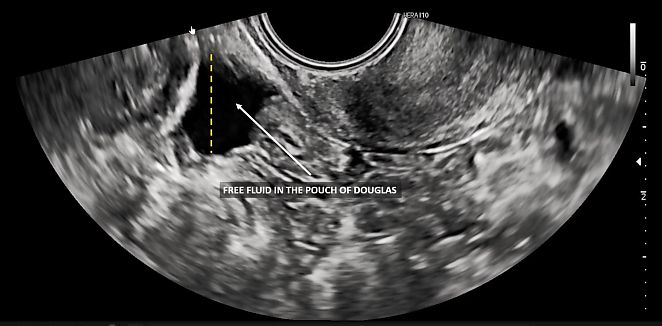

The pouch of Douglas (or rectouterine pouch) is the extension of the peritoneal cavity between the rectum and the posterior wall of the uterus. It is the deepest point of the abdominopelvic cavity and, as such, a site at which fluids and exudates are likely to accumulate.

The fluid level in the pelvis can be assessed with a single vertical measurement relative to the screen (Figure 8). The fluid may appear clear, or ‘anechoic,’ or may exhibit ‘low-level’ echogenicity. The amount of fluid can fluctuate throughout the menstrual cycle.

8

Measurement of fluid (dashed line) within the pouch of Douglas, showing a relatively small volume.

The peritoneum covering both the vesicouterine pouch and the pouch of Douglas can be a common site for superficial endometriosis, and it can also be affected by carcinomatotic nodules in the case of gynecological malignancy, such as ovarian or endometrial cancer.19